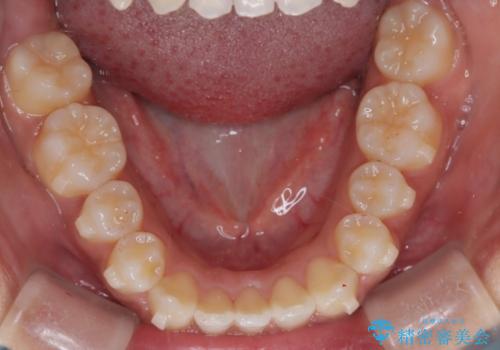

- 笑ったときに八重歯が見えることを主訴に来院されました。

下の前歯が一本足りない患者様でしたので、シミュレーションを作り、事前に患者様と治療ゴールのイメージをしっかり共有したうえでインビザラインを用いて治療を行っています。

奥歯を後ろのほうに動かすことで、前歯も少し下がることができ、矯正後の口元も満足していただきました。